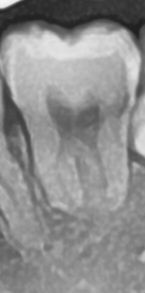

37번치아 충치있나요? 파노라마.

37번치아에 충치있나요 한 치과에서 37번 치아 충치급하다고하셔서 그런데 이 전에 치과4군데 어느곳에서도 이부분을 제대로 관찰안하신지 몰라도 37번치아에 충치가있다고 말씀하신적이없어서 많이 당혹스럽네요 아하 치과의사분들은 어떻게 생각하시는지요 고견을 듣고싶습니다 감사합니다

엑스레이 상으로는 큰 충치가 보이진 않습니다.

충치는 엑스레이 사진으로만 볼 수 있는 것이 아니라 육안으로 확인을 해야 하는 경우도 있기 때문에 치과에서 검진을 받아 보는 것이 좋습니다

뒤쪽으로 충치가 잇어 보이긴합니다. 하지만 정확히 판단하기 위해서는 사랑니 발치를 먼저 하고 다시 확인하셔야될것같습니다

뒤쪽 사랑니 머리가 두번째 어금니를 밀면서 영향을 주고 있는 상황은 맞습니다. 더불어 부분매복 사랑니이기 때문에 위생관리가 부족하여 치아, 잇몸 사이에 음식물이 잘 껴서 충치가 진행되었을 확률이 높긴 합니다만 위 사진만으로는 신경 옆 검은 부분이 충치의 양상이라고 단정지을 수 없습니다. 저정도 충치라면 바깥 구조 (아주 흰색, 법랑질)의 파괴가 확연히 보였어야 하는데 그러지는 않습니다. 일단, 파노라마 말고 치근단 방사선 사진 찍어보고 매복 사랑니에 대한 발치 후 해당 부위를 직접 눈으로 확인하는 것도 좋은 방법입니다.